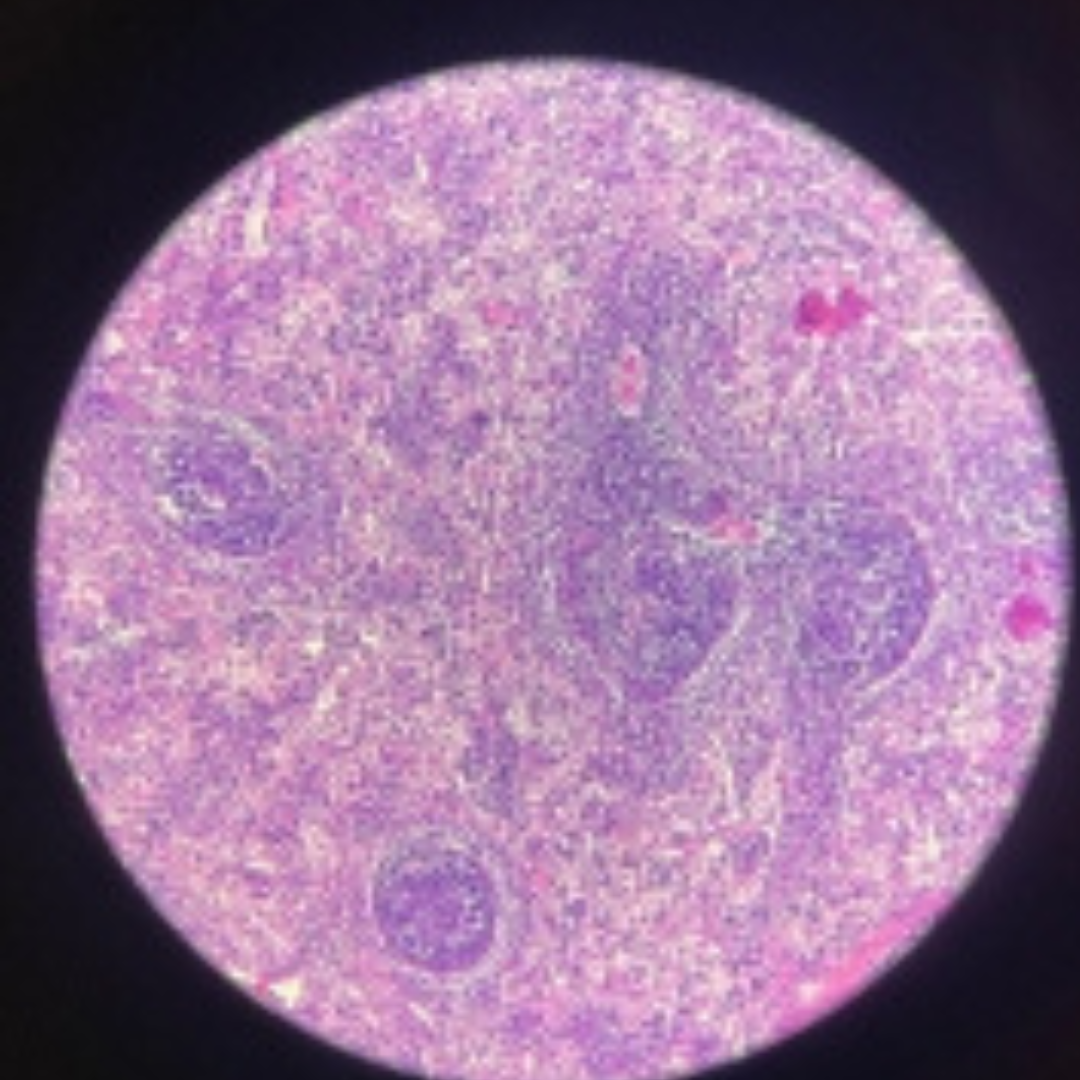

Lymph Node

11

New cards

Lymph Node

12

New cards

Lymph Node

13

New cards

Lymph Node

14

New cards

Lymph Node

15

New cards

Lymph Node